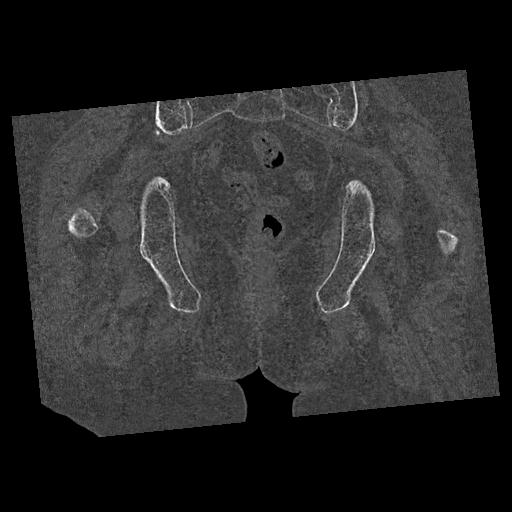

100703 1/27 両股正面+軸 1/29 両股正面+軸 94歳女性 パンソンロン

46666 1/28 両股正面+軸と 1/26 右手関節 2R 76歳女性 右転子部骨折

37 1/18 両股正面+軸 1/22 2R 86歳女性 右転子下

82084 1/14 1/20 股関節 2R 78歳男性 右人工骨頭

102811 1/13 股関節 2R 1/19 2R 80歳女性 右DHS

91569 3/25 両股正面とラウエン 70歳女性 人工骨頭+バンクーバー